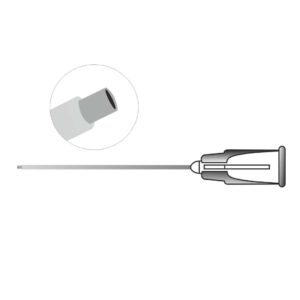

Description

A precision ophthalmic cannula designed for controlled fluid injection during cataract surgery to separate the lens nucleus from the capsule. It facilitates smooth nucleus rotation and safe cortical removal by creating a balanced fluid wave. Manufactured with a fine, atraumatic tip to ensure accurate hydro dissection and enhanced surgical control.

Available in disposable and Reusable